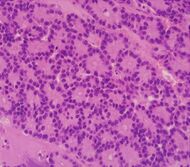

| نوع السرطان | الحدوث النسبي[11] | نتائج الفحص المجهري[11] | صورة مجهرية | علامات كيمياء الأنسجة المناعية [11] | التعديلات الجينية[11] |

|---|---|---|---|---|---|

| سرطانة الخلايا العنيبية الپنكرياسية (ACC) | 1% إلى 2% | المظهر الحبيبي | |||